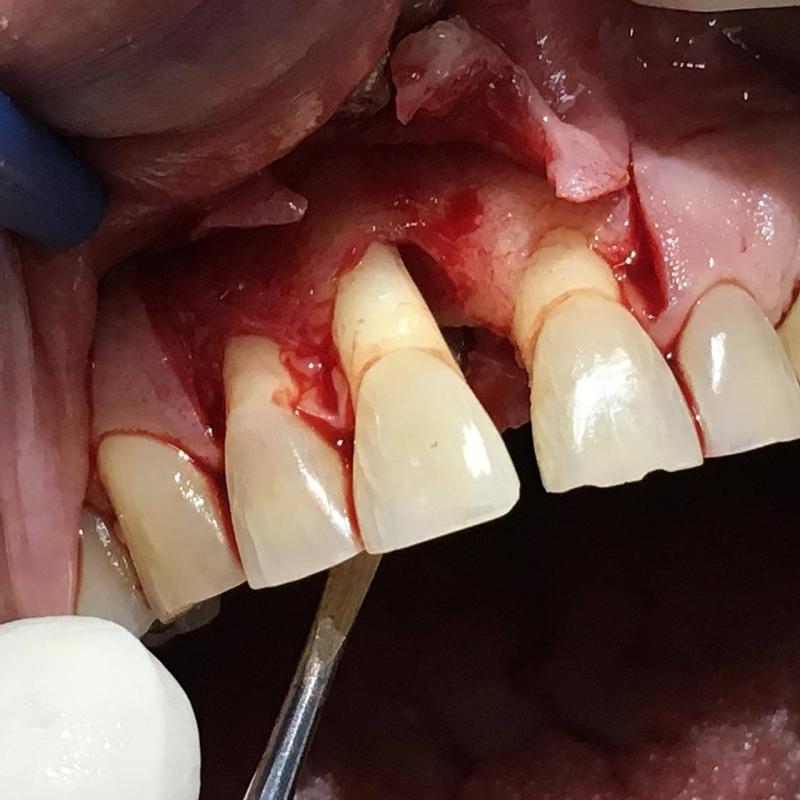

La parodontologia controlla il benessere delle strutture portanti dei denti (gengive e osso di sostegno) cercando di prevenire o curare la piorrea che nella popolazione adulta è la più frequente causa di perdita dei denti.

Oggi più che mai viene richiesta la copertura di esposizioni radicolari mediante la chirurgia estetica mucogengivale. Inoltre con la cura della piorrea si mantiene in buono stato la salute generale del paziente prevenendo complicanze cardiovascolari e diabetiche.